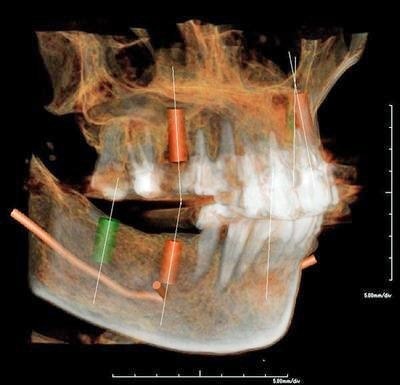

レントゲンでは把握できないことまでCTでは確認することが出来ます。

身体を断面や立体図として見ることが出来、骨はもちろんの事、神経や血管に至るまで確認することができます。

そのデータを元に、どのような角度、どのような深さでインプラントを打ち込むかなど、的確な治療計画を立てることができます。

CT・診断:5,000円(税別)※インプラント治療を受ける場合は無料